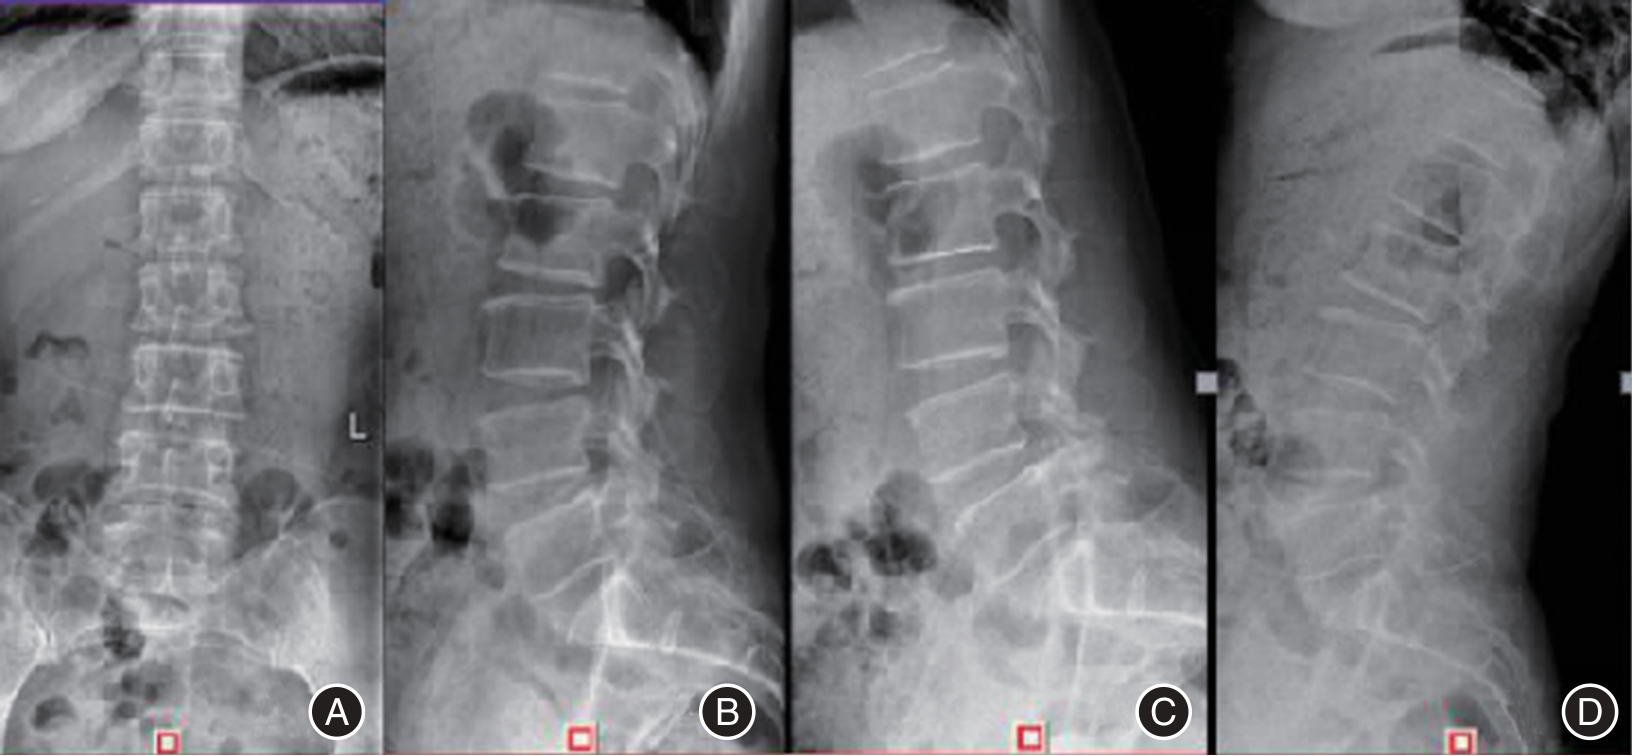

目的 探讨单一切口椎间孔镜治疗双节段腰椎管狭窄并腰椎间盘突出症的临床疗效。 方法 回顾性分析2016年3月至2018年5月在广西中医药大学第一附属医院脊柱骨伤科就诊的40例双节段腰椎管狭窄并腰椎间盘突出症患者临床资料,其中通过单一切口同时穿刺椎间孔镜治疗的患者11例(A组),通过单一切口前后穿刺椎间孔镜治疗的患者13例(B组),通过双切口前后穿刺椎间孔镜治疗的患者16例(C组)。记录患者的一般临床资料,三组不同时间点(术前、术后即刻、术后1周、术后1个月、末期随访)的VAS评分、JOA评分及临床疗效,并运用统计学进行分析。 结果 三组间手术时间、术中透视次数、皮肤切开长度和满意度差异均有统计学意义(P < 0.05);手术时间与手术方式在VAS、JOA评分上存在交互作用;手术时间、手术方式在VAS、JOA评分上存在主效应(P < 0.05);三组术后即刻、术后1周、术后1个月、末期随访与术前在VAS、JOA评分上比较差异均有统计学意义(P < 0.05);三组间术后即刻在VAS、JOA评分上差异有统计学意义(P < 0.05);三组间术后1周在VAS评分上差异有统计意义(P < 0.05)。 结论 单一切口椎间孔镜技术同时减压双节段腰椎管狭窄并腰椎间盘突出症的有效手段,具有手术时间短、术中透视少,损伤小等优势,患者满意,值得临床推广应用。

Objective To evaluate the clinical effectiveness of single?incision intervertebral foraminotomy in treating double?segment lumbar spinal stenosis accompanied by lumbar disc herniation. Methods A retrospective analysis was conducted on 40 cases of double?segment lumbar spinal stenosis and lumbar disc herniation treated in our orthopedic (spinal surgery) department from March 2016 to May 2018. Among these cases, 11 patients (Group A) were treated with percutaneous discectomy, 13 patients (Group B) underwent percutaneous endoscopic discectomy, and 16 patients (Group C) received double?incision percutaneous surgery. General clinical data for all patients were recorded. Visual Analog Scale (VAS) scores, Japanese Orthopaedic Association (JOA) scores, and clinical outcomes were assessed at five different time points: preoperatively, immediately postoperatively, one week postoperatively, one month postoperatively, and at the final follow?up. Statistical analysis was performed on the collected data. Results The operation time, the number of fluoroscopies performed on the hands, the length of the skin incision, and patient satisfaction were all statistically significant (P < 0.05). An interaction effect was observed between the operation time and the surgical procedure on both the VAS and JOA scores. Both the operation time and the surgical method had significant main effects on the VAS and JOA scores (P < 0.05). Significant differences in VAS and JOA scores were found among the three groups immediately post?surgery, one week post?surgery, one month post?operation, and at the end of the study (P < 0.05). Immediately after surgery, there were statistically significant differences in VAS and JOA scores among the three groups (P < 0.05). One week post?surgery, there were also statistically significant differences in VAS scores among the three groups (P < 0.05). Conclusions The single?incision intervertebral foramen technique is an effective approach for simultaneously addressing double?segment lumbar spinal stenosis and lumbar disc herniation through decompression. This method boasts a shorter operative duration, reduced intraoperative radiation exposure, and minimal tissue damage. Patient satisfaction is high, making it a valuable addition to clinical practice.